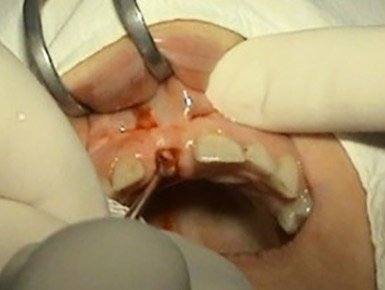

1. PHASE - implant placement